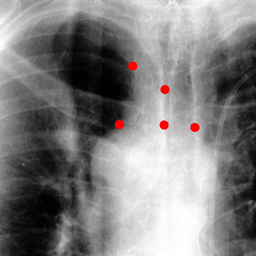

The dataset we use in the experiments is a cone-beam CT (CBCT) dataset captured for radiation therapy. The dataset contains 340 raw CBCT scans with each has 780 X-ray images. Each X-ray image comes with a geometry file that provides the registration ground truth as well as the information to reconstruct the CBCT volume. Each CBCT volume is reconstructed from the 780 X-ray images, and in total, we have 340 CBCT volumes (one for each CBCT scan). We use 300 scans for training and validation, and 40 scans for testing. The size of the CBCT volumes is 448×448×768448448768448\times 448\times 768 with 0.5 mm voxel spacing, and the size of the X-ray images is 512×512512512512\times 512 with 0.388 mm pixel spacing. During the experiments, the CBCT volumes are treated as the 3D pre-intervention data, and the corresponding X-ray images are treated as the 2D intra-intervention data. Sample X-ray images from our dataset are shown in Figure. Note that unlike many existing approaches [15, 17, 25] that evaluate their methods on small datasets (typically about 10 scans) which are captured under relatively ideal scenarios, we use a significantly larger dataset with complex clinical settings, e.g., diverse field-of-views, surgical instruments/implants, various image contrast and quality, etc.

We consider two common views during the experiment: the anterior-posterior view and the lateral view. Hence, only X-rays that are close to (±5°plus-or-minus5°\pm 5\degree) these views are used for training and testing. Note that this selection does not tightly constrain the diversity of the X-rays as the patient may be subject to movements with regard to the operating bed. To train the proposed method, X-ray and DRR pairs are selected and generated with a maximum of 10°10°10\degree rotation offset and 202020 mm translation offset. We first invert all the raw X-ray images and then apply histogram equalization to both the inverted X-ray images and DRRs to facilitate the similarity measurement. For each of the scan, we also annotate their landmarks on the reconstructed CBCT volume for further evaluation.

Refer to caption

Figure 6: Sample raw X-ray images of our dataset.